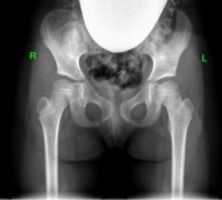

Рентгенограммы больной Т., 10 месяцев. Диагноз: врожденный вывих бедра справа.

2. Открытое вправление бедра в сочетании с транспозицией вертлужной впадины (подвздошной остеотомией таза)

Применяется у детей старше 1 года в тех ситуациях, когда врожденный вывих бедра сочетается с выраженным недоразвитием вертлужной впадины.

Разработанная нами методика подвздошной остеотомии не требует использования трансплантата. То есть, при фиксации фрагментов остеотомии тазовой кости нет необходимости в использовании чужеродных тканей или заборе собственного костного трансплантата.

«Способ хирургического лечения детей с патологией тазобедренного сустава» (патент РФ на изобретение № 2405486 от 10.12.2010 г.)